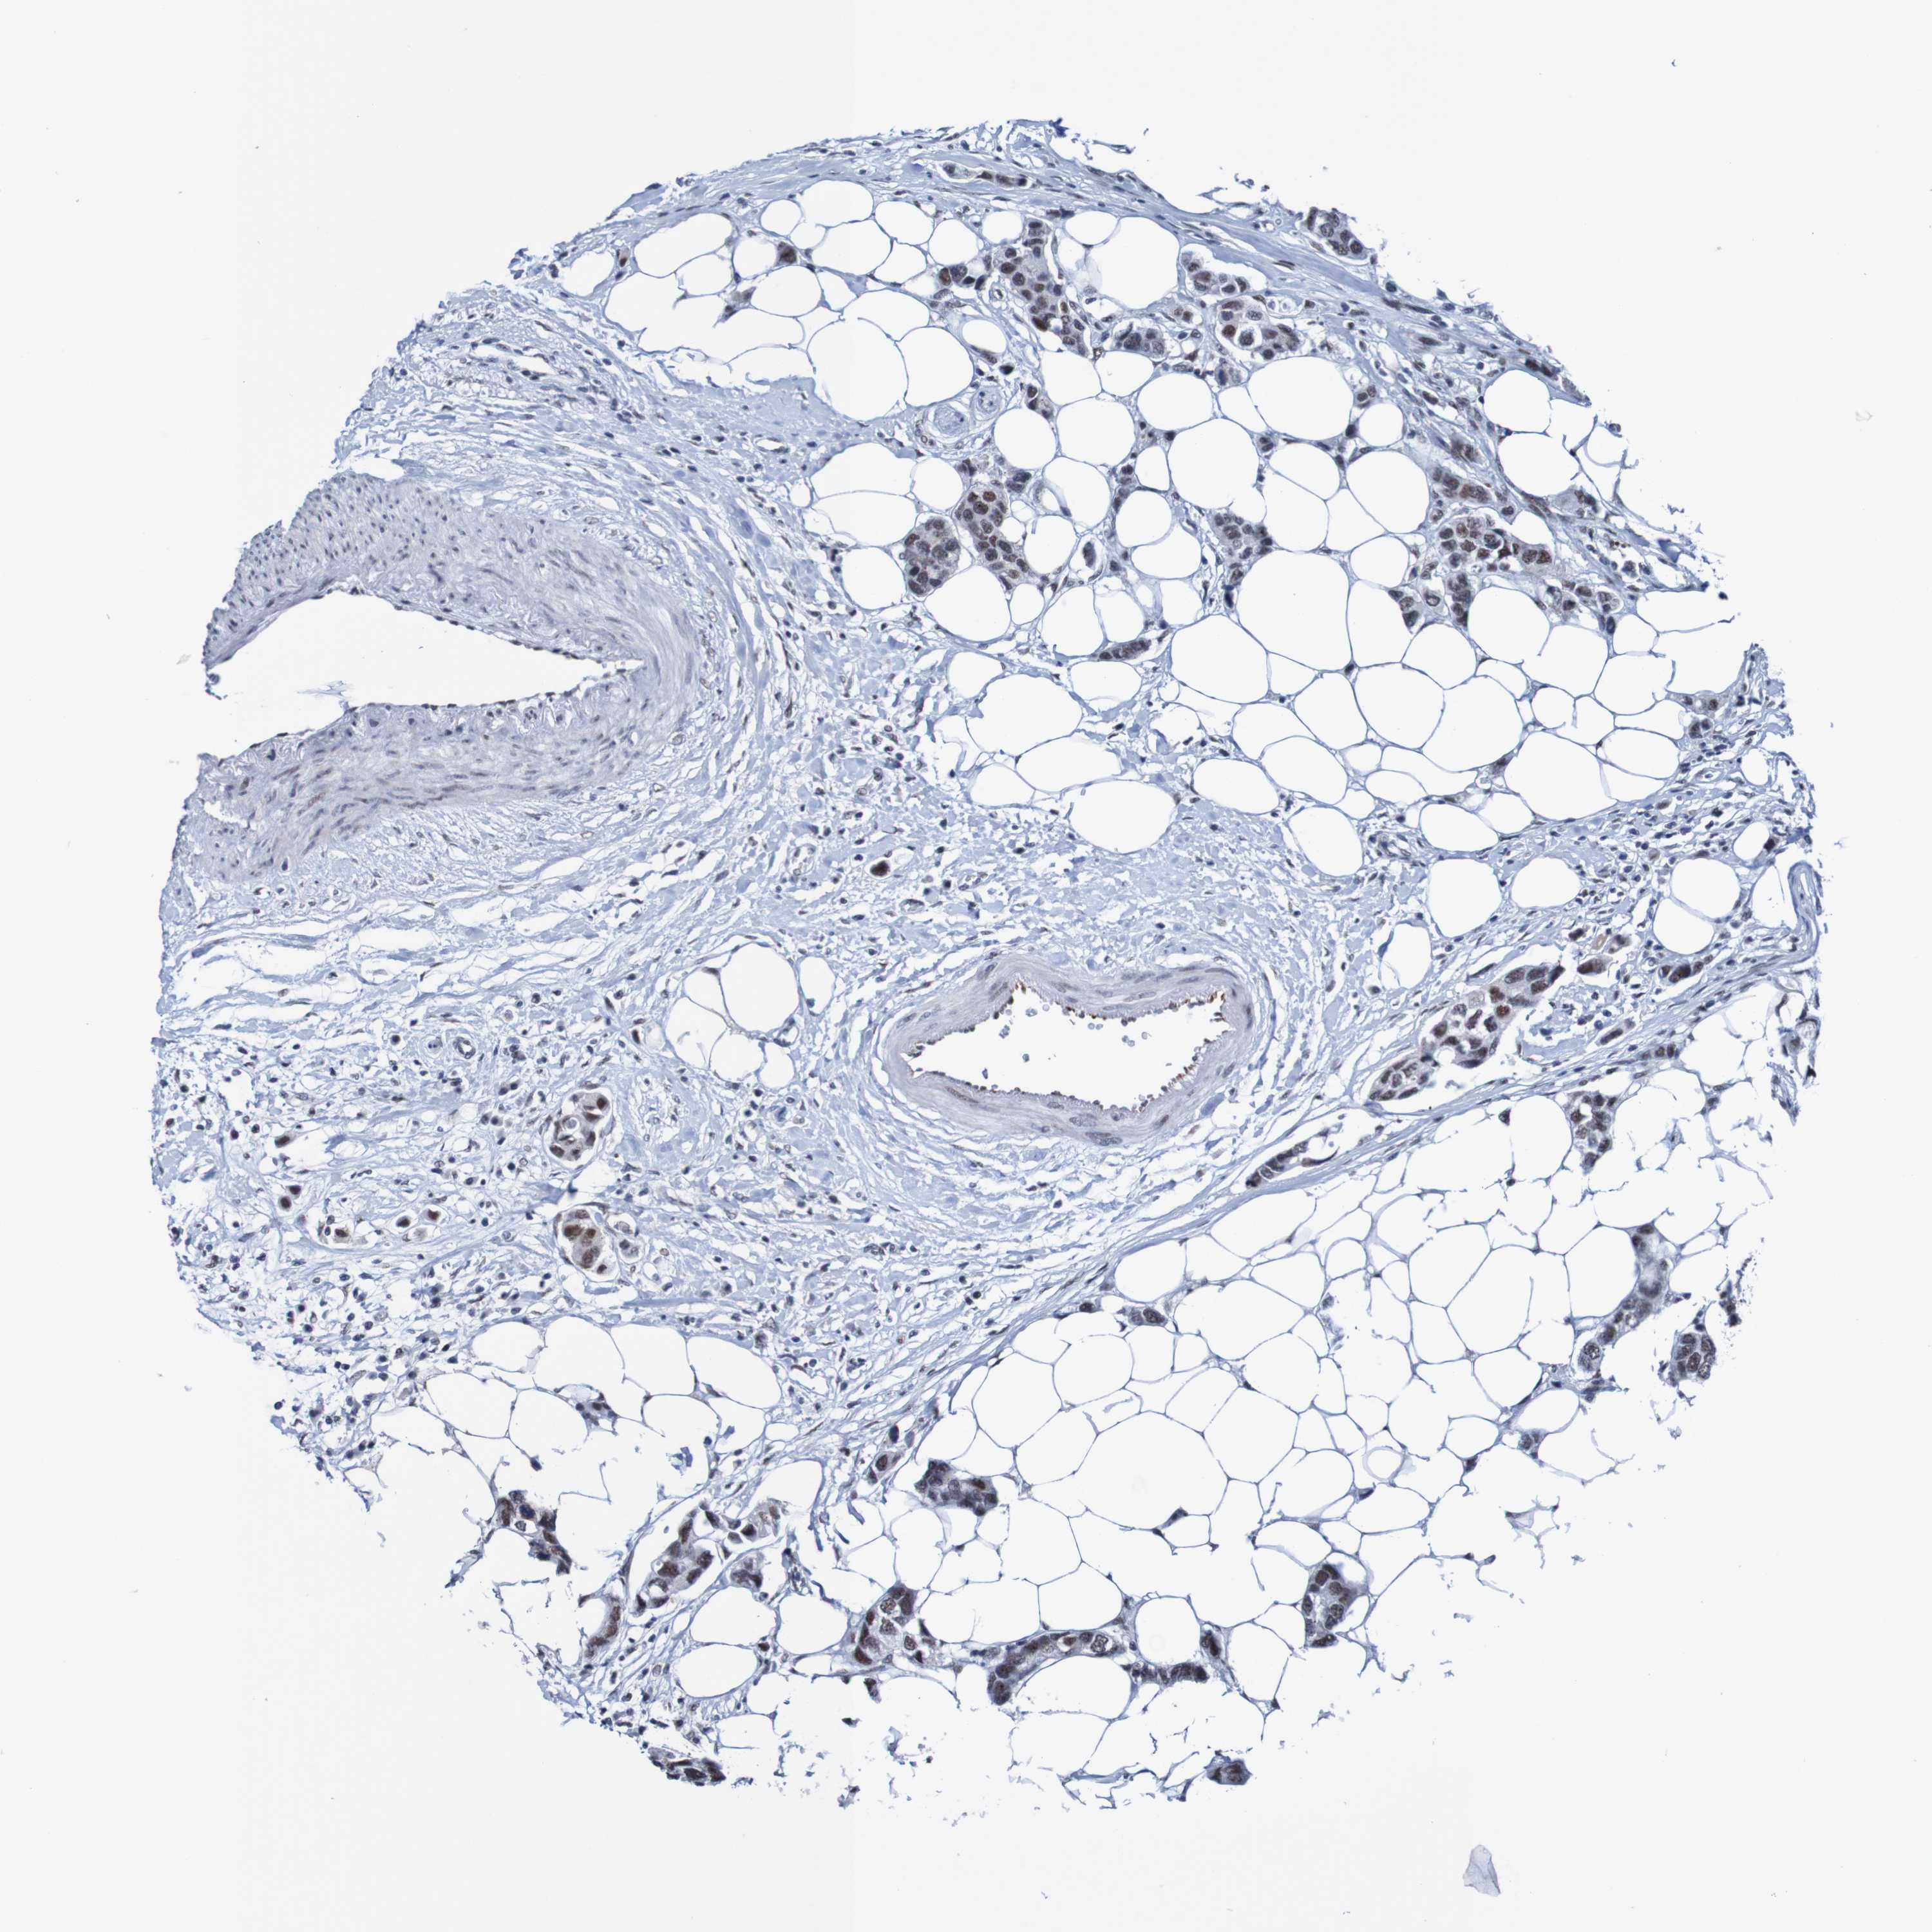

BRCA TCGA BRCA VALIDATION PROTEIN EXPRESSION